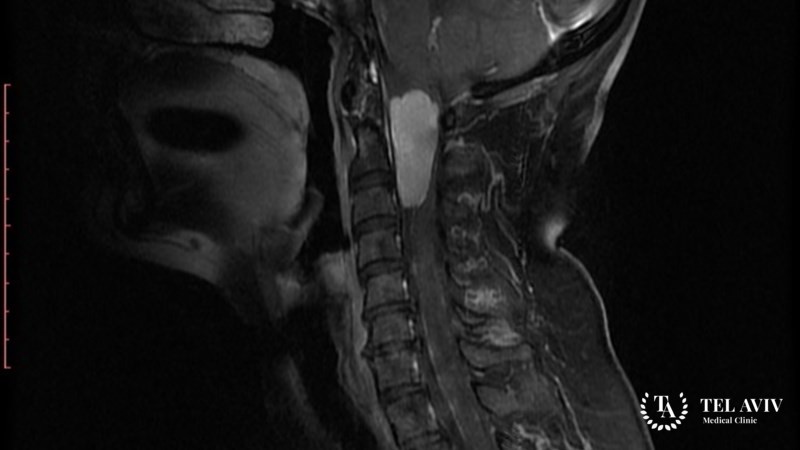

- Компьютерную томографию с использованием контрастного вещества;

- Магнитно-резонансную томографию.